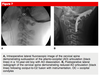

When would you consider endocrine WU for SCFE and what are you looking for?

child is < 10 years old

weight is < 50th percentile

- *hypothyroidism** (labs show elevated TSH)

- *renal osteodystrophy** (abnormal BUN and creatinine)

- *growth hormone treatment**